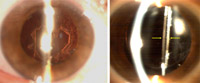

La agudeza visual de la paciente en el momento de la consulta era de 0’4 (10º x -1’25, -1’75) en su ojo derecho. La imagen biomicroscópica mostraba una córnea transparente, con una cámara anterior amplia y sin células (

Figura 1). La presión intraocular era normal. Bajo midriasis farmacológica, se observaba una distensión del saco capsular con acúmulo de un material transparente y una leve opacificación de la cápsula posterior (

Figura 2). La LIO estaba bien posicionada en el saco capsular sin apreciarse un desplazamiento anterior de la misma.

Figura 1. Imagen biomicroscópica inicial, sin dilatar. No se observan alteraciones aparentes.

Figura 2. Imagen biomicroscópica bajo midriasis. Se muestra un aumento del espacio retrolental y la cápsula posterior (flechas). El saco está repleto de un material transparente y se aprecia una leve opacificación de la cápsula posterior.

Se orientó el cuadro clínico como un síndrome de distensión o bloqueo capsular. Se practicó una capsulotomía posterior Nd:láser YAG (

Figura 3), apreciándose una inmediata disminución de la amplitud del espacio retrolental por el drenaje del material retenido a la cavidad vítrea. Una semana después, la agudeza visual corregida era de 0,8 sin evidenciarse una modificación de la refracción previa.

Figura 3. Imagen biomicroscópica tras la realización de capsulotomía Nd:YAG. El espacio retrolental ha disminuido considerablemente su amplitud.